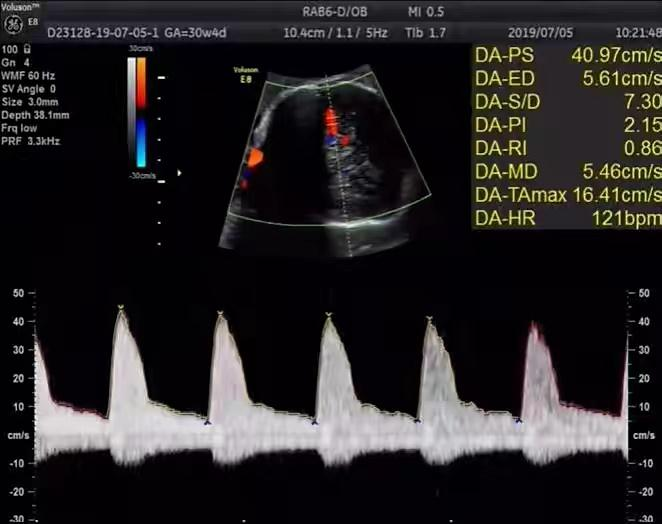

胎儿大脑中动脉(middle cerebralartery,MCA)血流频谱测定指标包括:阻力指数(resistance index,RI)、舒张末期血流速度(end diastolic velocity,EDV)、收缩期峰值流速(peak systolicvelocity,PSV)、PSV与EDV比值(S/D)及平均大脑中动脉血流速率(mean velocity,Vm)等。

正常妊娠时,胎儿大脑中动脉的PI、RI、S/D随妊娠月份增加而逐渐下降,RI正常0.7-0.9,平均0.80左右。

1.正常的脑循环为高阻力,胎儿出现宫内缺氧时大脑中动脉的RI和PI降低,而脐动脉RI和PI增高,提示大脑供血保护机制(微脑效应),此时,大脑中动脉的峰值流速增高。

3.缺氧早期大脑血液供应增加,颅内血管扩张,阻力降低,大脑中动脉多普勒频谱显示舒张末期血流速度增加,PI值下降,说明缺氧早期的血流再分配。

4.当大脑中动脉RI值、PI值明显下降,而脐动脉和腹主动脉的PI值升高,大脑中动脉PI值与脐动脉PI值的比值低于2个标准差时,提示严重缺氧的存在。